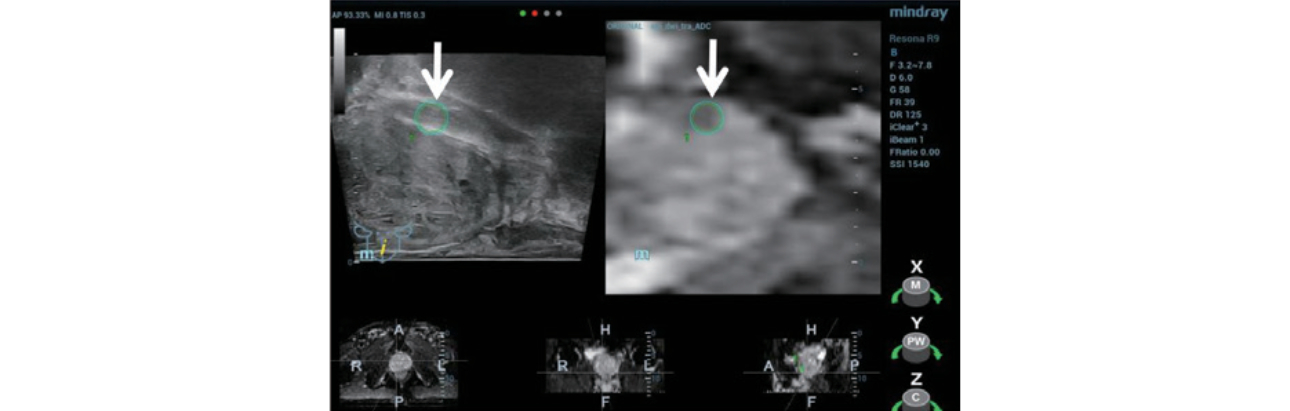

Step 1: The appropriate MRI sequence (Figure 2) was selected and the dataset imported onto the Resona 9 and into the live ultrasound exam.

Step 2:?Using MindrayŌĆÖs iFusion software, the TRUS and MRI images were aligned and fused (Figure 3) and the target was labeled (Figure 4).

Systemic biopsy is the current main diagnostic method for PCa. As the biopsy sites are standardized rather than targeted at a particular suspicious lesion, this method may also result in missed diagnosis or underestimation of disease. Multi parameter MRI has a high sensitivity and specificity for the diagnosis of PCa, however, MRI guided biopsy is complicated and expensive. Mindray iFusion software on the Resona 9 provides a solution by fusing the MRI dataset with live ultrasound imaging. Using bi-plane TRUS/MRI fusion guidance for targeted prostate biopsy improves the accuracy of clinical prostate cancer diagnosis [2].

In this case, the suspicious lesion was detected on MRI and using iFusion navigation the corresponding plane and target area were labeled on ultrasound. A CEUS exam provided additional diagnostic information and three guided biopsies were performed into the suspect area. While the standard 12-point samples were negative, one of the targeted samples came back positive for PCa. This case clearly shows how biplane TRUS/MRI fusion targeted biopsy can help avoid missed diagnosis and improve diagnostic accuracy.